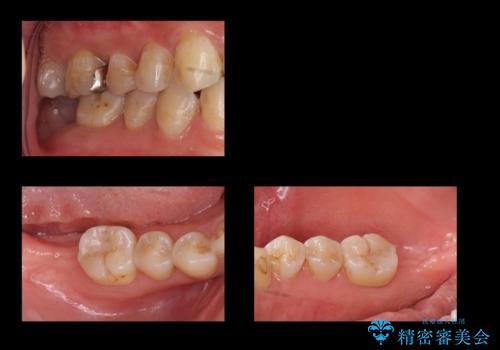

奥歯の歯ぐきからウミが出る 抜歯してインプラントへ

- 奥歯の歯ぐきからウミが出ている、抜歯が必要と他院で言われたとのことでした。

ただし、かかりつけではインプラント治療を行っていないため、病院を探したとのことでした。

抜歯を行い、インプラントを入れていきました。